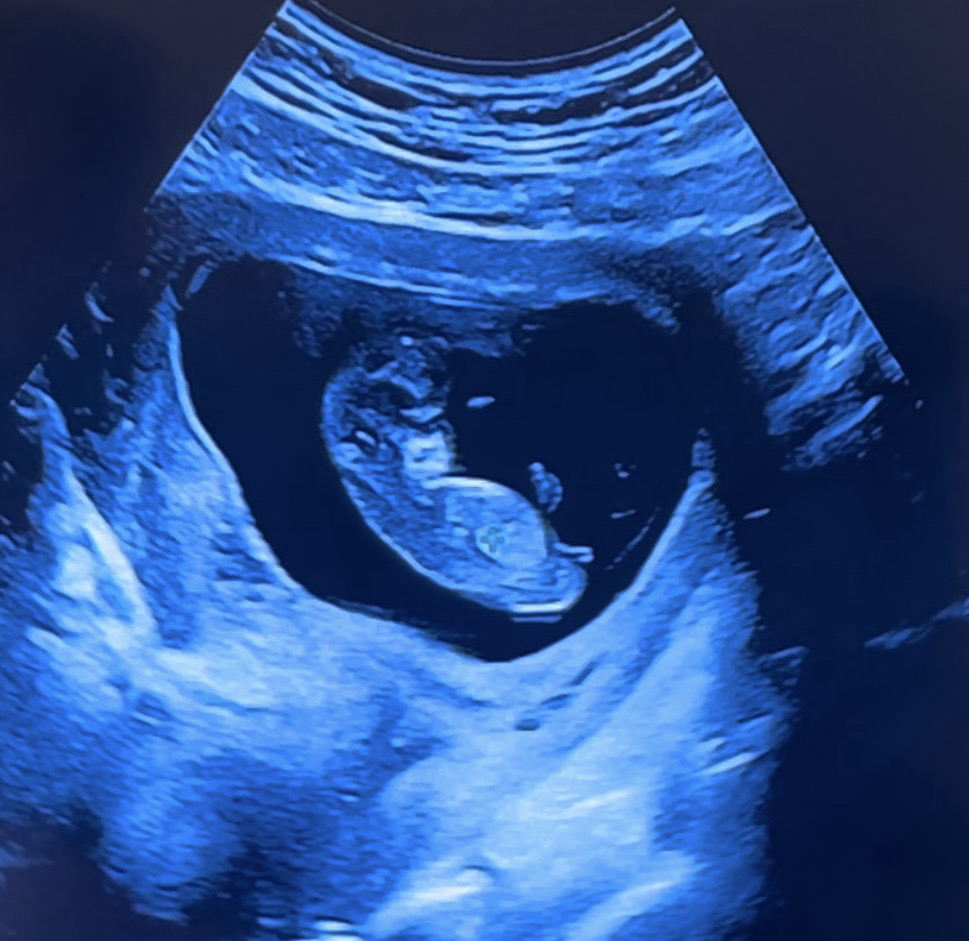

11주차 초음파 성별 너무 궁금해요!

오늘 11주 아기 초음파 하고 왔어요~ 성별이 너뮤 궁금한데 여러분들은 어떻게 보이세요~?

NIPT 검사 결과 아들이였어요..! 각도법이 안맞기도 하네요 ..! 댓글들 감사합니다!